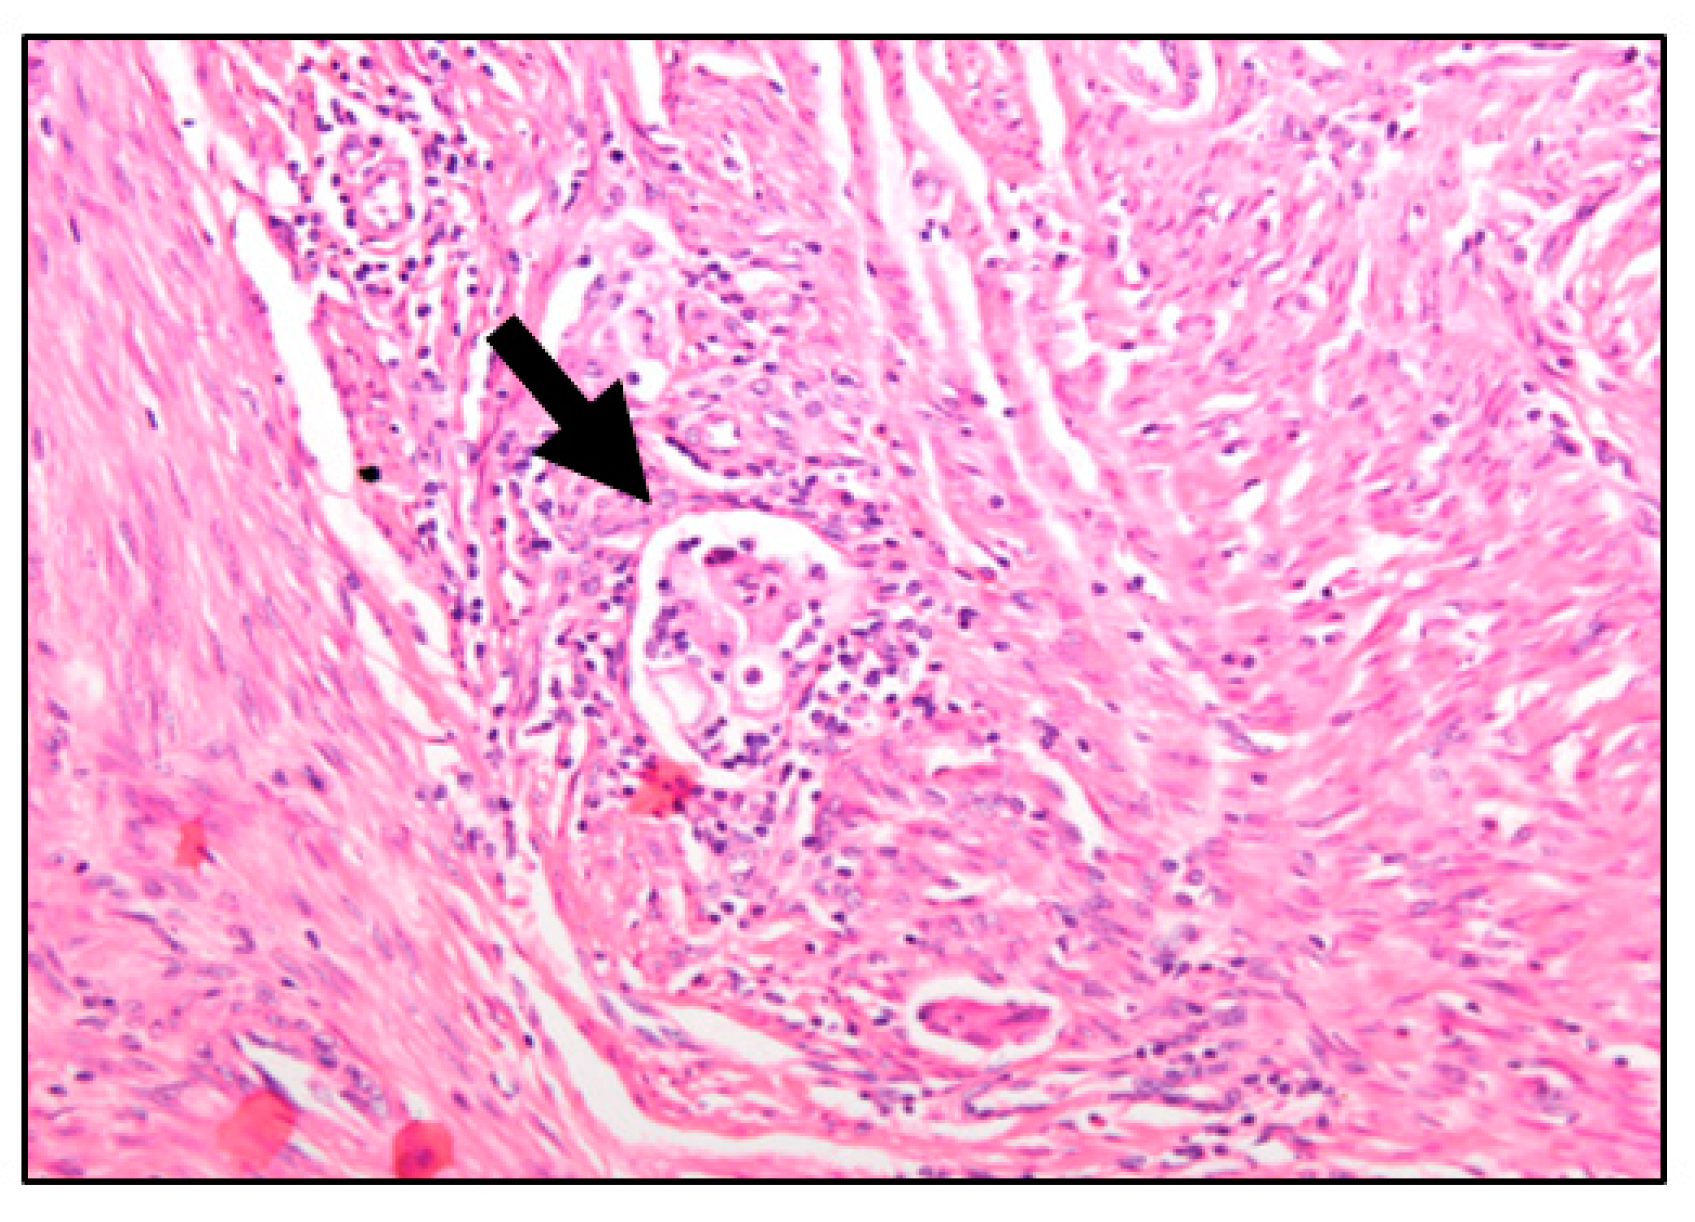

In this regard, lymphovascular space invasion (LVSI), defined as the presence of tumor cells within endothelial-lined channels outside the main tumor (Figure 1), has been postulated as one of the first steps in the metastatic spread of endometrial cancer [1,2,3,4]. Positive LVSI is significantly correlated with nodal metastases, shorter disease-free survival (DFS) and OS (1–8). For this reason, patients with low-risk features and positive LVSI are upgraded to the high-intermediate risk class for recurrence, and complete surgical staging with pelvic and paraaortic lymphadenectomy and/or adjuvant treatment is recommended [5,6]. Unfortunately, usually it is not possible to know LVSI status until a final pathology report. Even in that setting, LVSI diagnosis is linked to an observer’s experience [7]; yet there is a low rate of agreement between observers (kappa coefficient = 0.3) [7] and only moderate accuracy for LVSI on a frozen section (68.3–92.4%) [8,9].

Figure 1.

Hematosylin-eosin-stained section from an endometriosis endometrial tumor (magnification 20×). Lymphovascular space invasion can be observed (arrow): Cohesive tumor cells within a space surrounded by endothelial cells.